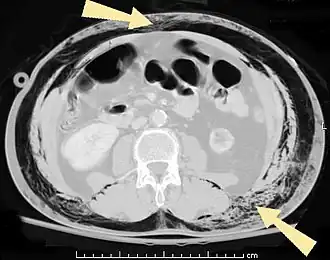

КТ брюшной полости пациента с подкожной эмфиземой (указано стрелками) | |

Подко́жная эмфизе́ма — скопление воздуха в подкожной клетчатке грудной стенки, распространяющееся на другие области тела. Является симптомом повреждения лёгкого или воздухоносных путей[1].

В результате анатомической особенности клетчатки — отсутствия фасций — воздух довольно быстро распространяется на грудную клетку, шею, лицо, а также вниз на живот до мошонки (у мужчин) и бёдер[2].